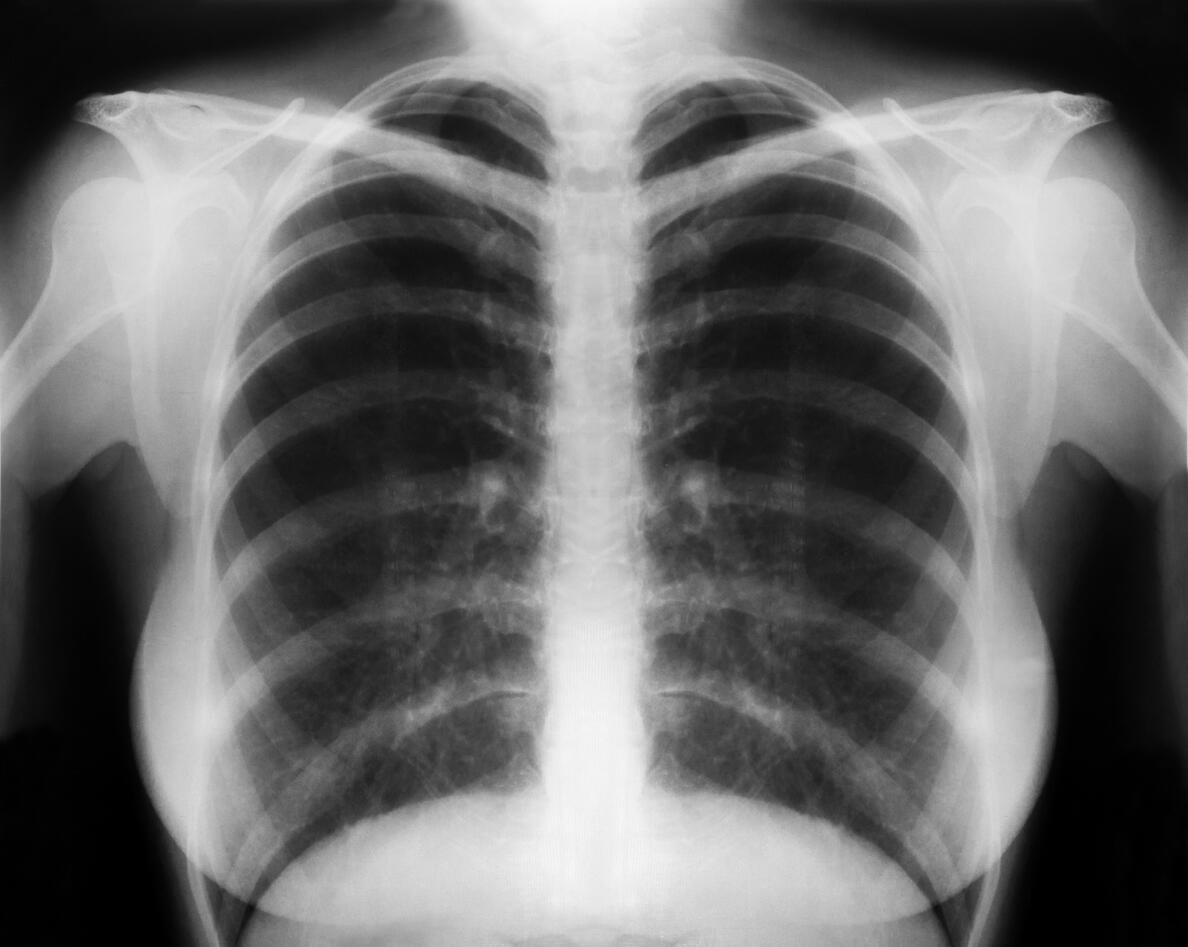

Even healthy adults harbour a diverse fungal environment in their lungs, as shown in a new study from researchers at the University of Bergen, Norway (UiB) published in PLOS ONE. The prevalence and severity of fungal infections have increased in recent years, and the Norwegian scientists have been examining fungi in both healthy and people with lung diseases.

The lungs were for a long time considered to be sterile in health, while in diseases like chronic obstructive pulmonary disease (COPD) failure in immune mechanisms were thought to allow microorganisms to proliferate and persist. New sequencing techniques have shown that several microorganisms reside in the lungs of healthy individuals, as well. Few studies have examined the fungal community in COPD and compared it to healthy controls using such techniques. According to the study findings, the compositions of these environments seem to be unaffected by the use of inhaled steroids.

The Bergen COPD Microbiome study (short name "MicroCOPD") is the world’s largest single-centre study on the fungal community in lungs of persons with COPD. The Bergen Respiratory Research Group collected samples from the lungs of 233 individuals with and without COPD using bronchoscopy. Lung and mouth samples from 193 of these individuals were subsequently sequenced to detect residing fungi.

"Results showed that both healthy and diseased lungs had a different fungal composition than the mouth, suggesting that lungs have a unique fungal environment", says PhD candidate Einar Marius Hjellestad Martinsen at the Department of Clinical Science.

The lungs were dominated by the fungus Candida. Interestingly, there were no differences in compositions between lungs from healthy individuals and patients with COPD. Furthermore, patients with COPD using inhaled steroids did not have any differences in the fungal community of their lungs compared to those not using inhaled steroids.